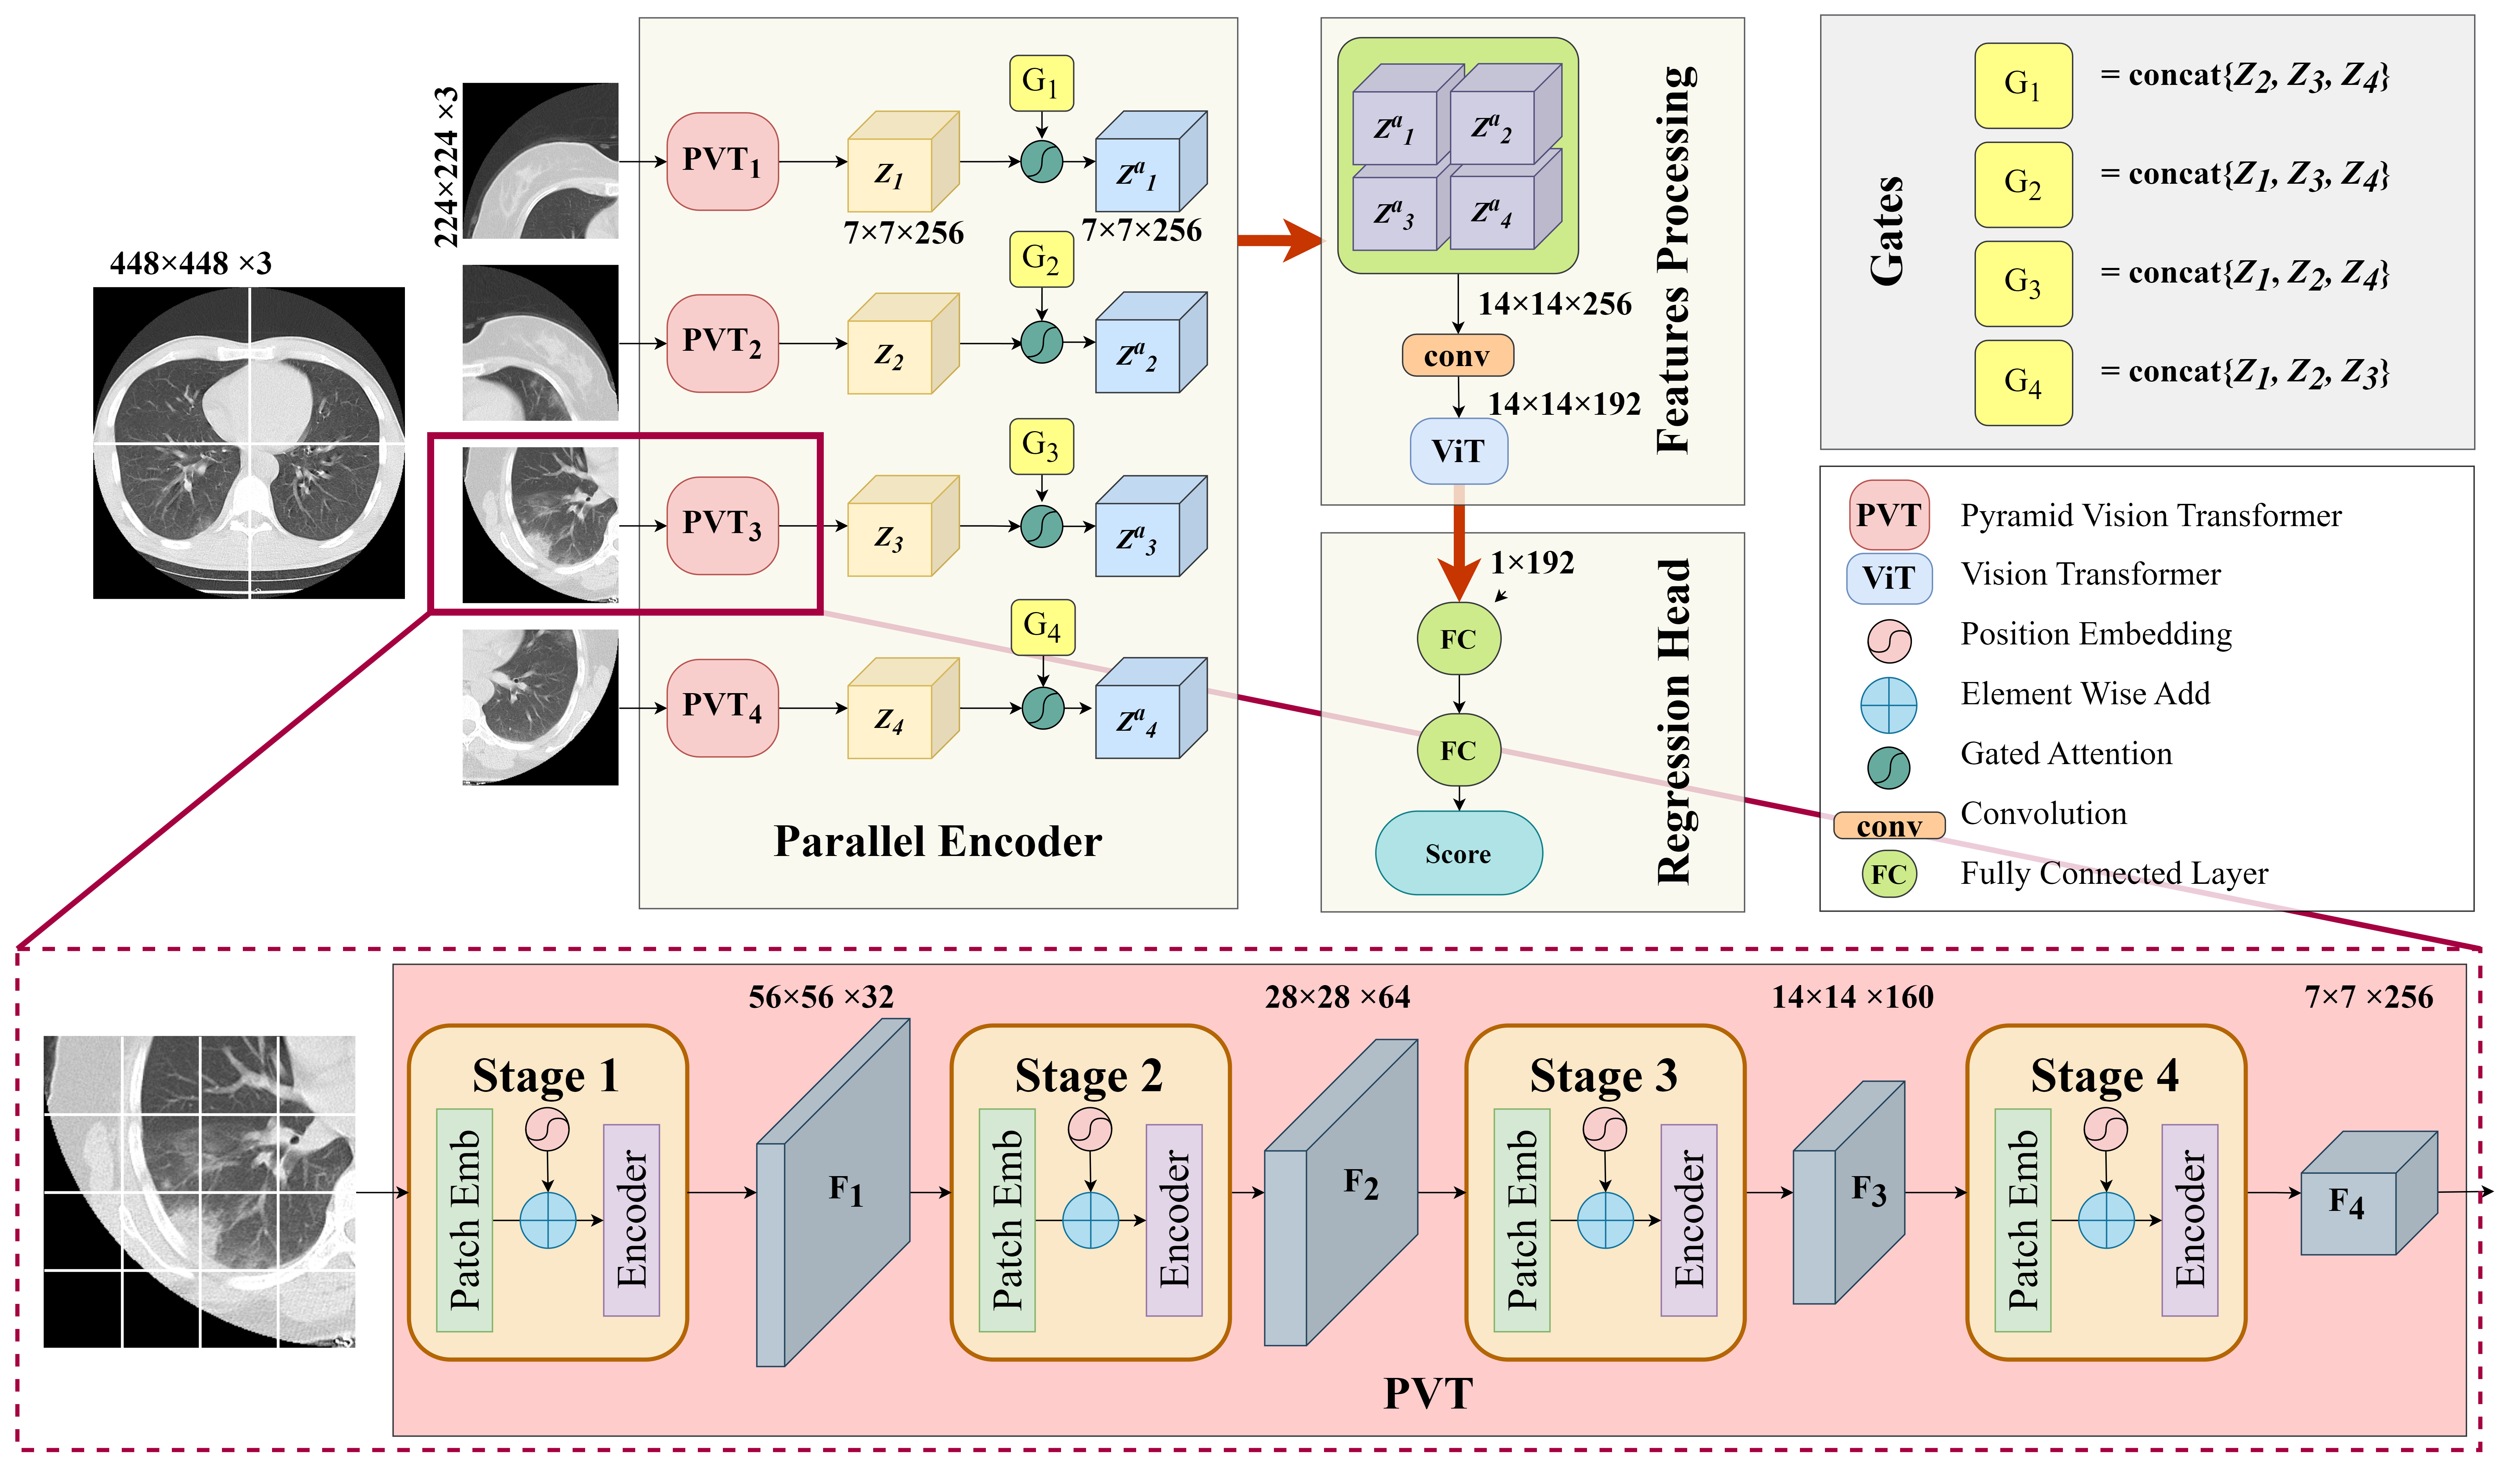

In this paper, we propose a new approach for predicting the severity of lung infection in pneumonia, called Quarter Cross-Attention PVT (QCross-Att-PVT), which is evaluated on two medical imaging modalities. As illustrated in Figure 1, our method consists of three main components: (1) an encoder constructed using parallel transformers with gated cross-attention mechanism, (2) a feature processing module, and (3) a regression head that outputs a scalar value representing the severity of the infection. This design allows the model to simultaneously capture and integrate diverse features from different regions of the input images, improving its ability to extract both local and global information and leading to a more comprehensive assessment of lung disease severity.

The input image is partitioned into four equal quadrants, then each is processed independently by a Transformer block. The obtained features from the four quadrants are then processed using our cross-attention gate to capture inter-region dependencies. The encoder is designed with a parallel architecture, where it processes the input through multiple pathways simultaneously.

In more details, the input image is firstly resized to dimensions of and then divided into four separate regions. Each region, with dimensions , is input into a Pyramid Vision Transformer (PVT) [52]. The PVT is an advanced model that adapts the Vision Transformer (ViT) architecture to better handle image recognition tasks, particularly by addressing limitations in capturing multi-scale features. Instead of traditional Multi-Head Attention (MHA), the PVT encoder employs Spatial-Reduction Attention (SRA) to enhance computational efficiency while maintaining strong feature representation. Similar to MHA, SRA processes queries, keys, and values, with significantly reducing the spatial complexity by downsampling keys and values before the attention operation. This reduces memory and computational costs, allowing the model to handle larger input feature maps. The PVT model processes the input through a hierarchical structure with four stages (), where each stage has different embedding dimensions, depths, and attention heads. The output size at each stage is given by:

| (1) |

where is the patch size and is the number of channels after the stage. At each stage, the resolution is further downsized with each reduction capturing increasingly broader contextual information as shown in Figure 1. The final output of each PVT typically has a small spatial resolution with a deeper representation, providing a rich representation that combines global context with fine-grained details.

In our setup, , , , and . The channel size in the third stage reflects an experimentally optimized balance between feature richness and computational efficiency, particularly when used with corresponding multi-head attention settings , which aligns with the scale of these channels. The input image is divided into four sections, resulting in four 3D feature tensors . Each of these tensors is then processed using an cross-Attention Gate (CAG). As depicted in Figure 2, the CAG is defined by the following expression:

In this equation, the inner convolutional layers perform linear transformations using convolutional blocks, which adjust the number of channels in the input and gating signals and to intermediate feature representations with a new channel count for and , respectively. The features derived from and are combined and passed through a third convolutional layer, producing a 2D weight map. The sigmoidal activation function is then used to learn the spatial attention coefficients for each patch token. These spatial coefficients are applied to the encoder’s feature maps , representing element-wise multiplication.

For each set of extracted features from one-quarter of the input image , the gating signal is formed by concatenating the features extracted from the other three quarters, while the features from the current quarter are used as the input signal. The output features for the first quarter are determined by the following equation:

| (3) |

where is the output produced by applying the attention gate to , the tensor, where is the input signal and acts as the gating signal. In this context, for each , is defined as the concatenation of the other output tensors of the other three tensors. i.e, , , , and . The operation performs cross-attention between the tokens of the current image region and those of the other three regions. This involves calculating attention scores between tokens from different regions, allowing the model to assess the relative importance of tokens across various parts of the image.

3.1.2 Features Processing and Regression Head

The resulting tensors from the four quadrants are concatenated along the spatial dimension. Specifically, the four tensors resulting from the four partial images are grouped horizontally and vertically, as shown in Figure 1. A convolution layer is then applied, followed by an additional Vision Transformer (ViT). This additional ViT is used to process the combined features and serves as a feature aggregator. It further refines the information extracted from the different regions before the final prediction of the severity is performed. Finally, a regression head consisting of two fully connected layers that map the cls features of the ViT into a single scalar representing the predicted severity score, as shown in Figure 1.